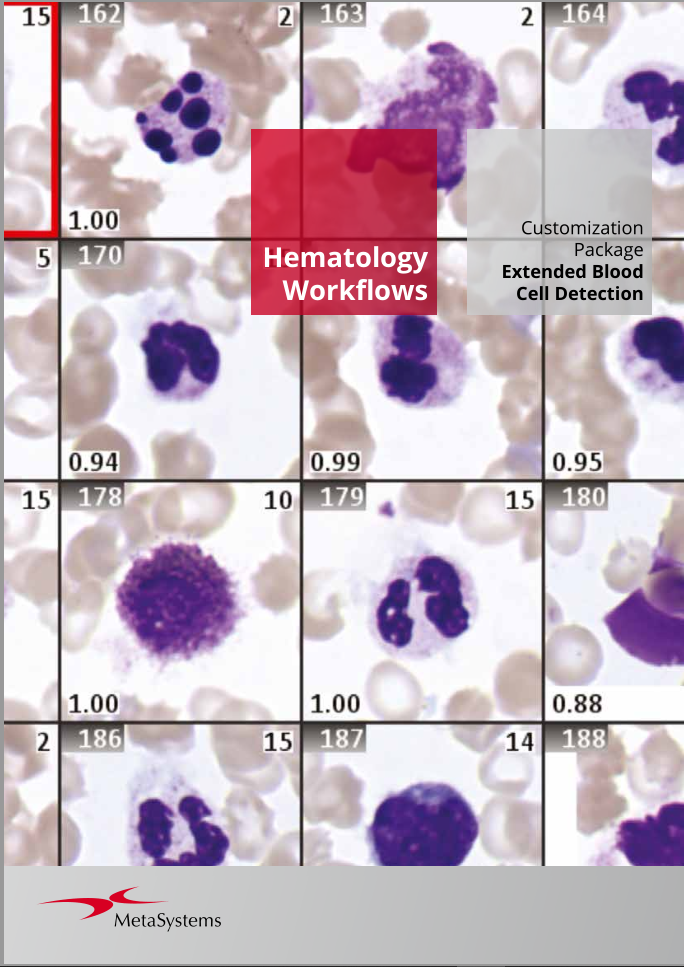

- Customize workflows according to your preferences using a flexible classifier-based imaging approach.

Utilizing the Metafer software, imaging systems scan specimens of diverse sizes, employ various contrasting methods and magnifications, and identify, classify, and enumerate cells or other objects. Metafer's modularity and flexible architecture make it proficient in assisting users from various fields with their specific imaging tasks.

Given the variability of each microscopic sample, automated imaging demands flexibility. Metafer's distinctive concept provides an effective solution: user-trainable classifiers accurately establish imaging standards, and by selecting the relevant classifier, the integrated scanning system swiftly transitions to the next task.